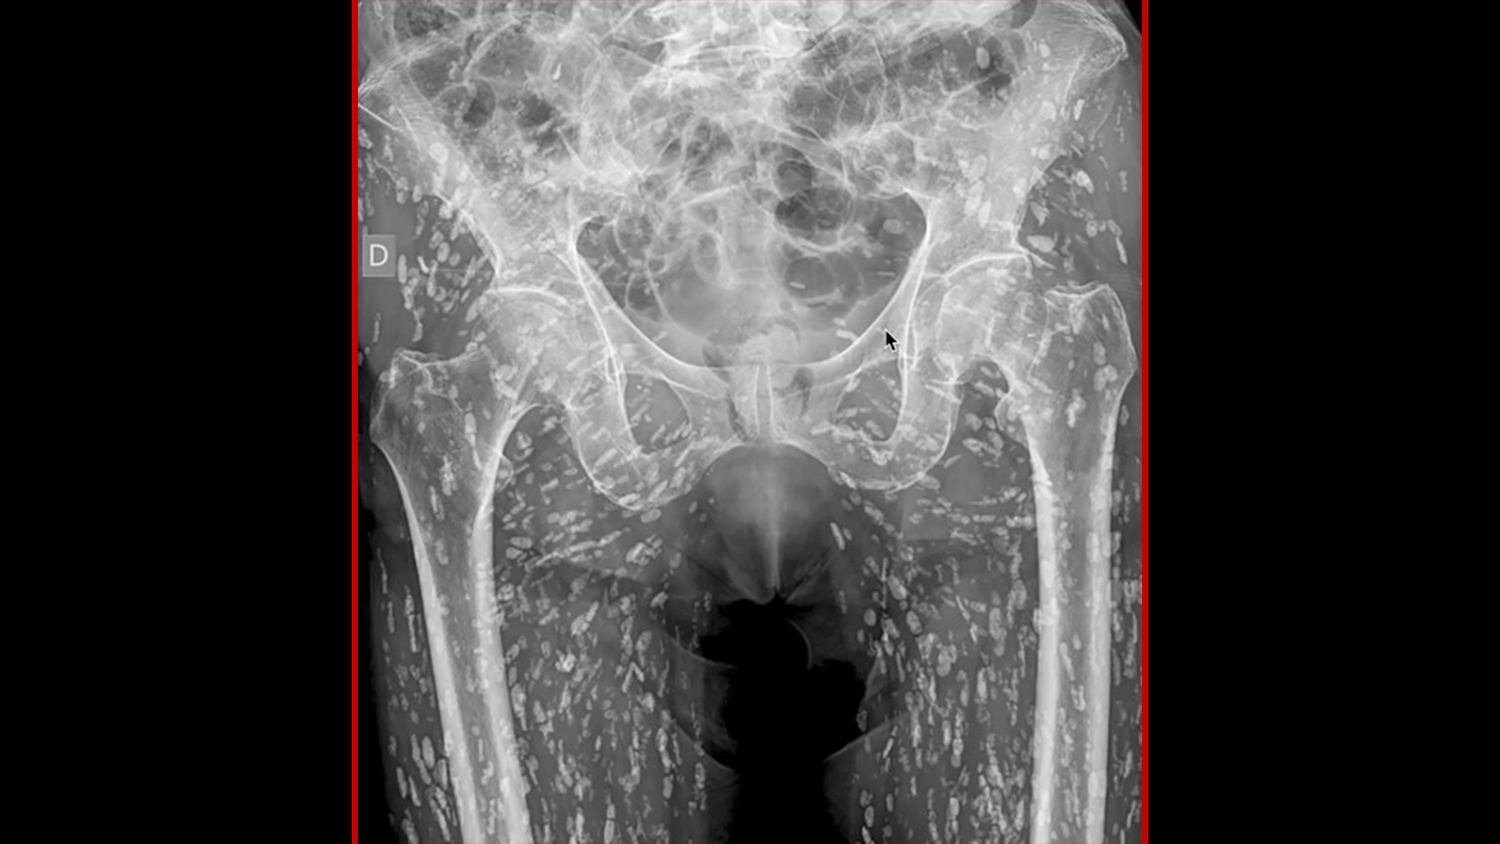

Eigentlich kam der Patient wegen Hüftschmerzen nach einem Sturz ins Spital. Das Röntgen zeigte, dass seine Hüfte und Beine voller Zysten war.

Ein Bild von verkalkten Parasiten im Gewebe eines Patienten hat sich viral verbreitet, nachdem der Arzt Sam Ghali aus Florida (USA) den Scan auf der Plattform X (ehemals Twitter) geteilt hat. Ghali beschrieb das Bild als eines der "verrücktesten Röntgenbilder", die er je gesehen hat. Der Scan zeigte die Hüfte und Beine des Patienten, die mit unzähligen länglichen Verdichtungen durchsetzt waren, die einem inneren Hagelsturm ähnelten. "Das ist eine Krankheit, die als Zystizerkose bekannt ist. Dabei handelt es sich im Wesentlichen um Larvenzysten von Taenia solium – auch bekannt als Schweinebandwurm."

Er erklärte, dass der ungenannte Patient die Krankheit nach dem Verzehr von rohem oder unzureichend gekochtem Schweinefleisch entwickelte, das Bandwurmlarven hatte. Die Larven – frisch geschlüpfte Würmer – gelangen in das Körpergewebe und bilden dort Zysten. Dies kann in verschiedenen Organen sowie in den Muskeln, der Haut, den Augen und dem zentralen Nervensystem geschehen. Das kann die Erkrankung Zystizerkose verursachen.

Im Fall dieses Patienten infiltrierten sie die Muskulatur und das weiche Gewebe der Hüfte und der Beine und verkalkten. Unglaublicherweise wusste der Patient gar nicht, dass er an der Krankheit litt. Er hatte sich nach einem Sturz aufgrund von Hüftschmerzen zum Röntgen ins Krankenhaus begeben.